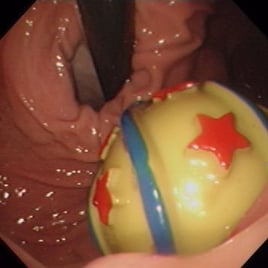

Grasping forceps are similar to biopsy forceps but have rat-tooth (Figure 3A) or alligator jaws that open wider. However, they rarely open wide enough to grasp rubber balls. The wires in basket forceps have a “memory”, so they spring open and can be steered over the FB by moving the endoscope tip before grasping it (Figure 3B). Very large baskets are available for large FBs, such as tennis balls, but again, these are often too large to pull out of the stomach via endoscopic removal.